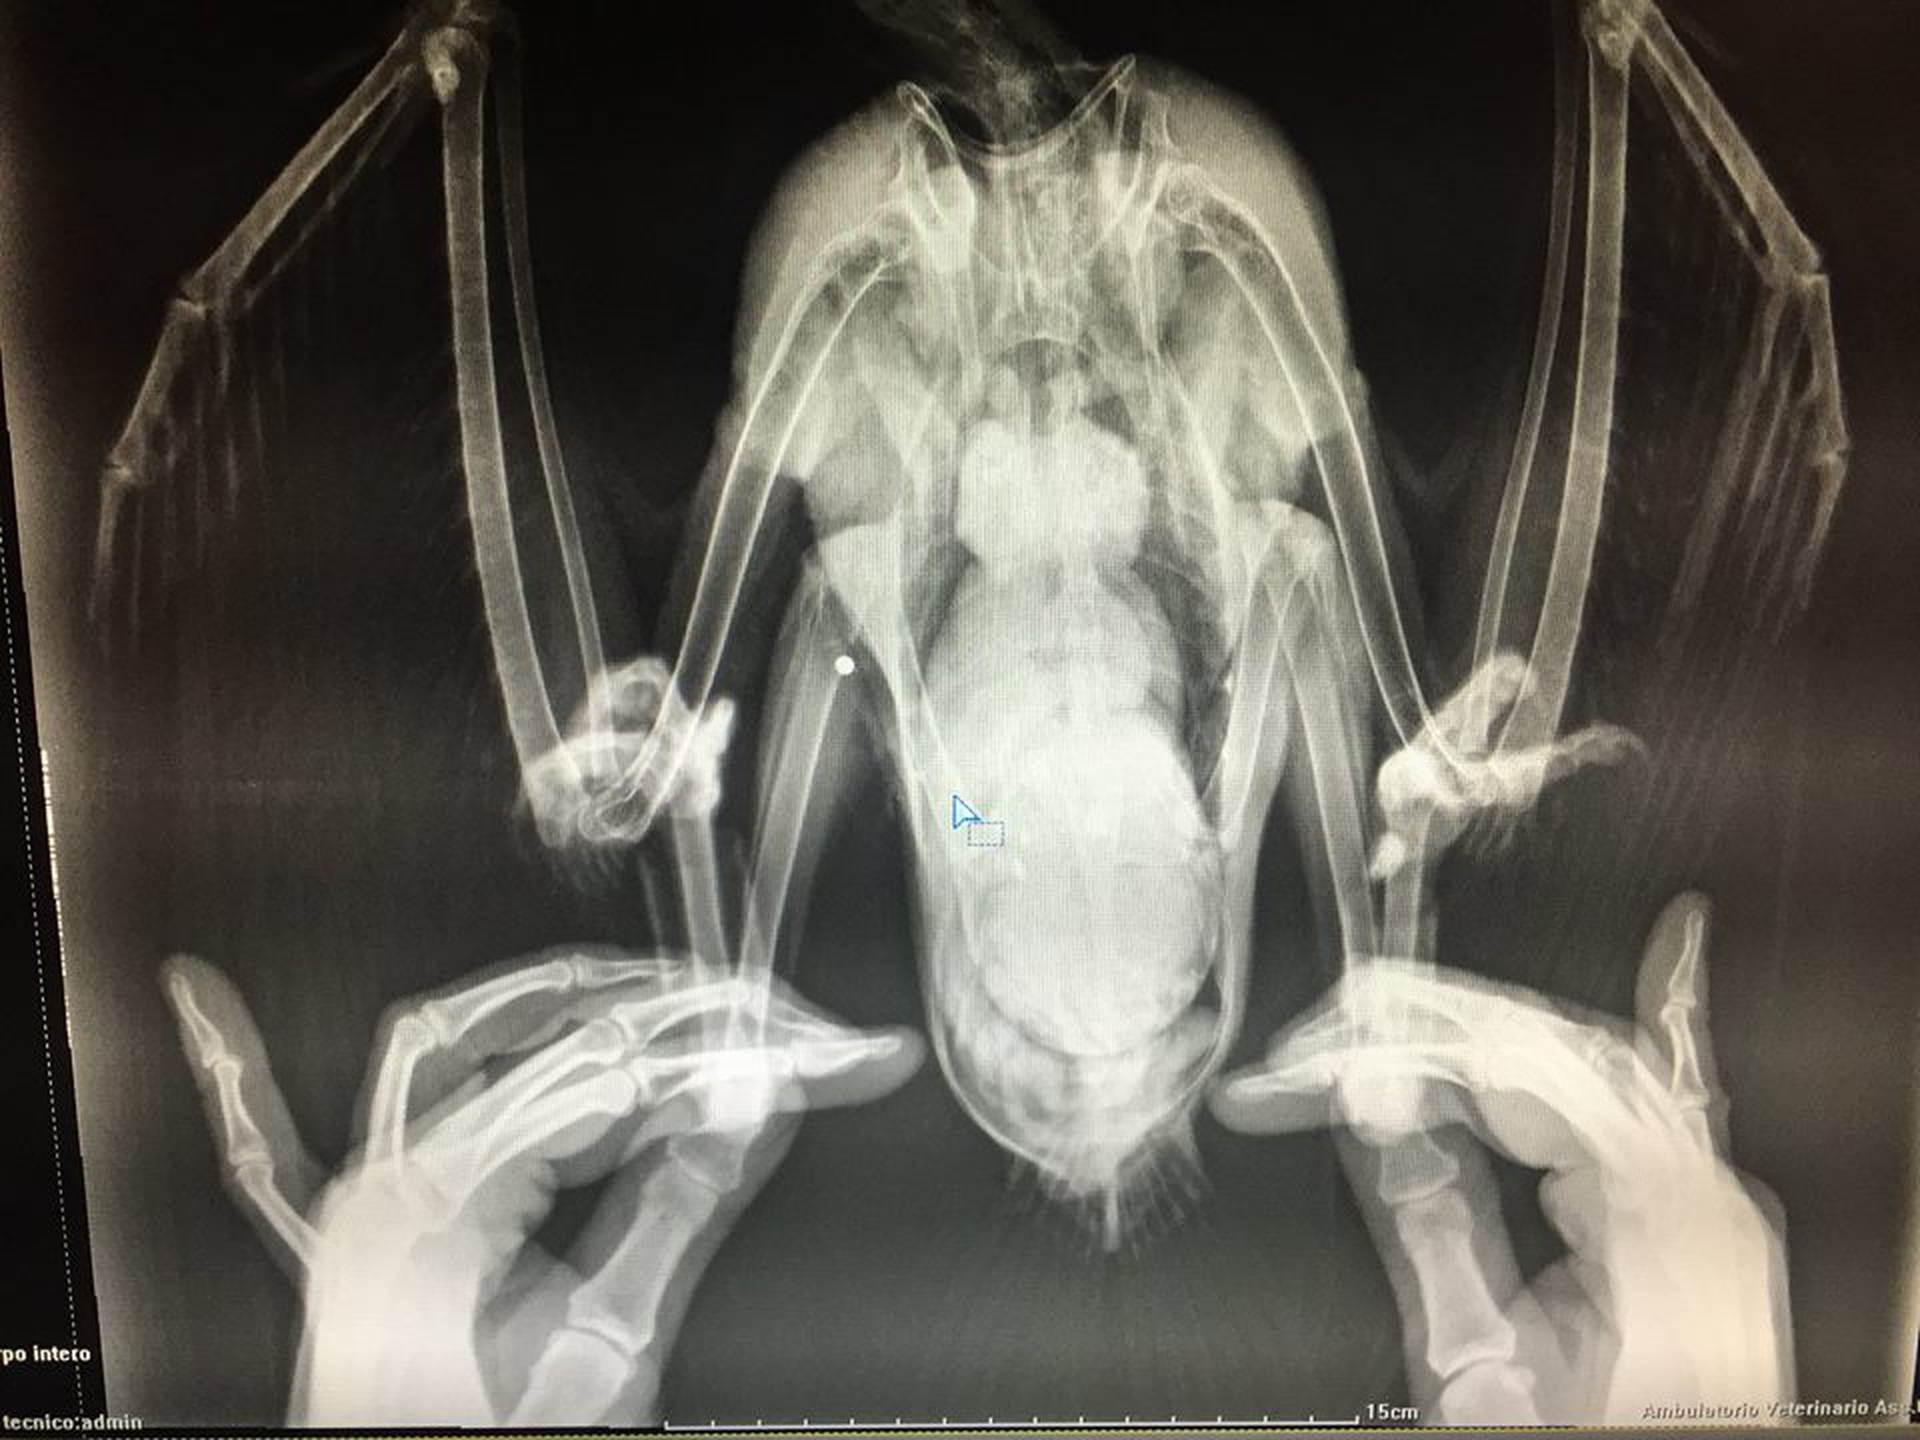

Kato, Tara, Enno – l’ultimo colpito nel bresciano – non ce l’hanno fatta, mentre Thor, colpito da una decina di pallini non potrà più migrare e verrà portato ad Orbettello per far parte del gruppo stanziale. Luna è stata l’ultima colpita, il 15 novembre scorso. “Gli organi vitali di Luna sono stati miracolosamente mancati dal colpo di fucile del bracconiere, che invece ha provocato una frattura completa al terzo prossimale della tibia, immediatamente immobilizzata per evitare altri traumi”, spiega il veterinario Camillo Sandri. Trasferita d’urgenza nella stessa clinica di Bolzano in cui si trova anche Thor, ibis già colpito a fucilate il 5 ottobre scorso in provincia di Grosseto, Luna verrà sottoposta ad intervento chirurgico già nelle prime ore di questa mattina. “Ci vorranno alcuni mesi di degenza e di immobilità totale, ma speriamo in buone probabilità che la prossima primavera Luna possa riunirsi al gruppo che migra verso l’Austria per la stagione mite”.

“La radiografia effettuata dal veterinario Camillo Sandri del Parco Natura Viva, evidenzia ferite alla zampa ed all’ala causate da pallini da caccia”, dichiara Johannes Fritz, a capo del progetto. “Si tratta quindi del quinto caso di bracconaggio. Quasi il 30 per cento dello stormo che da settembre sta attraversando l’Italia è stato abbattuto”.